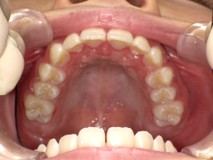

Before

After

【小学生】マイオブレース矯正 上顎前突(出っ歯)と叢生(でこぼこ)を改善

治療期間

2年

治療開始

8歳

種類

マイオブレース矯正

使用装置

機能矯正装置 咬合斜面版

現在は終了後8年たっていますが、今も定期健診にきてくれて 歯並びを保っています